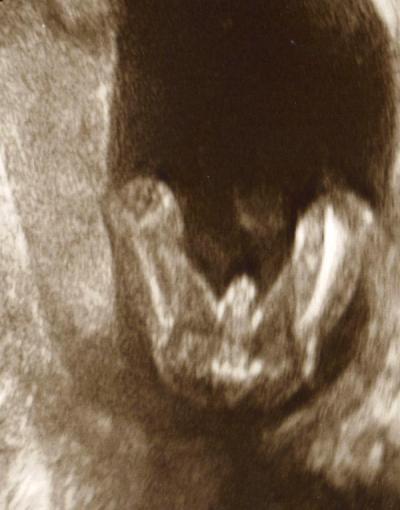

Hallo, ich bin nun in der 19. Woche schwanger, und letzte Woche meinte meine Gyn, es wird ein Junge. Ich habe mir das Beweisfoto hinterher immer mal wieder angesehen, und zweifelte vorerst nicht an ihrer Einschätzung. Nun war ich am WE bei einer Feier und eine Anwesende meinte beim Blick auf das Ultraschallbild, dass es für sie nicht 100% Junge wäre... sie sieht da 2 Striche... was für Mädchen spricht..und der angebliche Schniepel wäre die Nabelschnur, denn der ist doch ziemlich breit und dick für einen kleinen Jungen in dieser Woche. Nun hab ich das Internet durchforstet, aber keine echten Antworten bekommen. Darum frag ich mal in die Runde... Hier das Beweisfoto 17+1 SSW

Das ist eindeutig ein Junge Lg

Ich halte das auch für einen eindeutigen jungen :-) LG Kerstin

Das ist sowas von ein Junge ![]() Sieht man doch eindeutig. Bei meinen Mädels stand nichts "ab vom Körper", als wir zum Outing waren.

Sieht man doch eindeutig. Bei meinen Mädels stand nichts "ab vom Körper", als wir zum Outing waren.

Hey, ich habe 3 Jungs und ich würde auch tippen, dass es ein Junge ist.(Mir ist das Bild sehr vertraut. ![]() Mir wurde das auch immer schon etwas eher als 19.Woche so gesagt und so gezeigt.)

3 weiße striche bedeutet mädchen. nicht zwei. (durch die aneinanderliegenden schmalippen). gib mal bei google "3 weiße striche ultraschall" an. dann wirst du sehen was für ergebnisse kommen. die sehen deinem keineswegs ähnlich... ich vertraue außerdem der erfahrungen meines arztes, der täglich ultraschall-bilder erkundet. und nicht "laien", die selber nur ihre eigenen bilder kennt... wir bekommen übrigens auch einen jungen, und unseres sieht ähnlich wie deines aus.

Schaut aus wie ein junge! Ich häng mal ein bild von meiner kleine aus der 18 ssw an ;) da sieht man die striche, aber 100% war es damals noch nicht, weil sie soooo gezappelt hat. Hab es erst richtig in der 28 ssw erfahren. Aber dein bild ist ja mal echt eindeutig :)

Direkt wo der mauspfeil ist, da sind die 3 streifen ;)

eindeutig junge Weiß nicht wo man da 3 bzw 2striche sieht... lg

na da wollte deine bekannte sich wohl mal ganz wichtig machen ohne Ahnung zu haben. das ist wirklich ein eindeutigis jungs-outing. die Nabelschnur sieht etwas anders aus im us und im bewegten Bild wird dein Arzt die Situation erst recht anders beurteilen können.

Also ich tippe: es ist ein Junge Kaffeebohne sieht anders aus, von denen hab ich die letzten Jahre ganz viele Fotos gesehen...